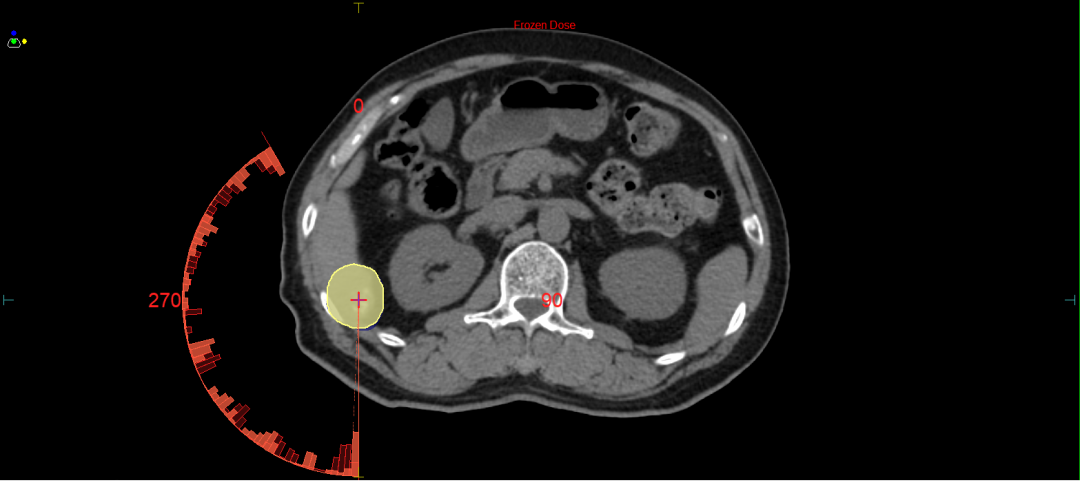

另一例肝肿瘤患者在呼吸门控技术辅助下,行超高剂量率的立体定向放射治疗,使肿瘤靶区剂量分布均匀性提升20%,周围正常肝组织受量降低35%。这些突破性成果在本次培训班上得到了国内放疗领域专家的高度评价。

图5 高精度动态放射外科,突破传统加速器在物理精度上的限制,应用于肝癌放疗。